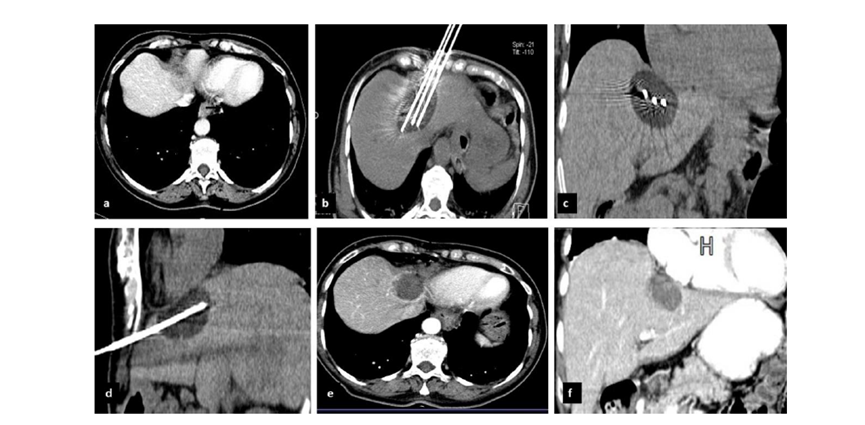

CT引导的冷冻消融

冷冻消融胆囊附近肿瘤病灶

(A)动脉期 MRI 显示胆囊附近有外周增强病变(箭头)。

(B)手术过程中 CT 显示冷冻探针位于病灶内。

(C)消融后,术后 1 个月CT 显示完全消融(箭头)。

undefined

冷冻消融肝包膜下肝细胞癌

(A)动脉期CT图像显示有一个包膜下结节(箭头)。

(B)门静脉期CT图像显示病灶区(箭头)。

(C) 在手术过程中的CT显示一个冷冻探针位于病灶内。

(D)消融后,术后1个月影像CT显示完全消融。